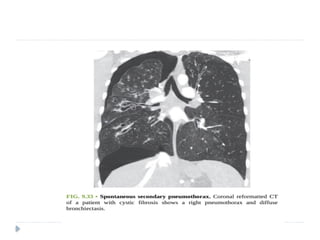

 A pneumothorax developing without a

precipitating traumatic event in a patient with

predisposing lung disease is said to be a

spontaneous secondary pneumothorax .

 Chronic obstructive pulmonary disease is the most

common cause of secondary spontaneous

pneumothorax.

 pneumothoraces are associated with lung

metastases.( sarcomas most common) ,and some

cystic lung diseases.

 CT

 Provided lung windows are examined, a

pneumothorax is very easily identified on CT, and

should pose essentially no diagnostic difficulty.

 pneumothorax is imaged as air in the pleural

space outside the lung and visceral pleura.

 Even a very small pneumothorax is visible in the

anterior pleural space.

 Its diagnosis is usually straightforward, although

differentiating a medial pneumothorax from

pneumomediastinun may be difficult in some

cases.